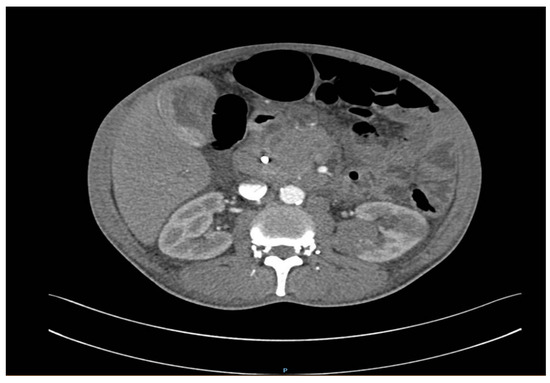

2. Detailed Case Description

2.1. Diagnostic Evaluation